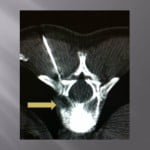

Vertebroplasty in the case of a fracture on posterior material implants

This type of vertebral fracture raises the problem of the entrance way and of the reduced visibility in lateral scopy of the filling of the secondary vertebral at the artrodesis material. The scannographic volume acquisition and the spotting has a large importance to guide the progress of the trocar without being blocked by the arthrodesis screws. The trocar path is outside the screws. An iterative scanner control checks the correct lateral position and the progression in the vertebrae to position at the level of the third anterior and third posterior. The filling is performed in the same way as standard vertebroplasty, the visualization of the cement by continuous lateral scopy is blocked by the osteosynthesis material, for this reason the injection must be done very carefully by alternatively controlling with scanner cuts the correct diffusion of the cement. The scanner control can also be blocked by the artifacts of the osetosynthesis material. Moreover in the cases of osteopenic fractures on arthrodesis, a low density line can exist around the screws showing a potential mobility of the material. In this case, the scanner guide can be very useful to position the tip of the trocar in front of this line. Thus, the vertebroplasty has the additional function to fix the intra vertebral corporeal arthrodesis.

Only the scannographic cuts allow to confirm the correct diffusion around the screws. The clinical results in out series are stackable to the vertebroplasties in the frame of the hyperalgic osteopenic fractures.